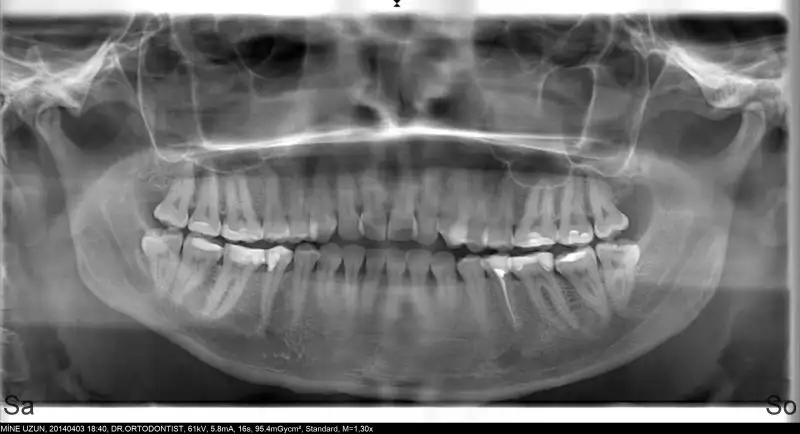

dişime tel takılmadan önce cekılen panaromık röntgen ve 2 sene sonra cekılen röntgende aradaki fark cok belli ..

ilk resimde diş kökum kıvrıkken sonradan o kıvrıklıkta öteye gecınce duzleştiğini görüyorum :) iki resmide ekliyorum :)